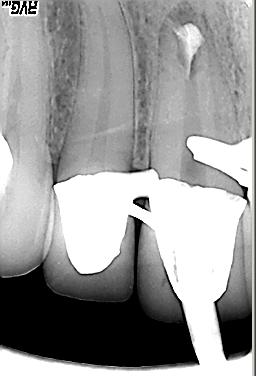

Röntgenologischer Ausgangsbefund im September. 2002 mit alio loco durchgeführter WF. Beide Wurzeln weisen eine apikale Parodontitis auf. Auch in der Furkation ist eine deutliche Resorption zu erkennen. Der Patient hat massive Schmerzen und einen stark herabgesetzten Allgemeinzustand

Röntgenmeßaufnahme

Röntgenmeßaufnahme nach vorgängig durchgeführter endometrischer Längenbestimmung. Nach der ersten Behandlung trat zunächst eine Verbesserung der Symptomatik auf. Nach ca. einer Woche kam es zu einer akuten Exacerbation mit lingualer Abszeßbildung. Der Abszeß wurde inzidiert